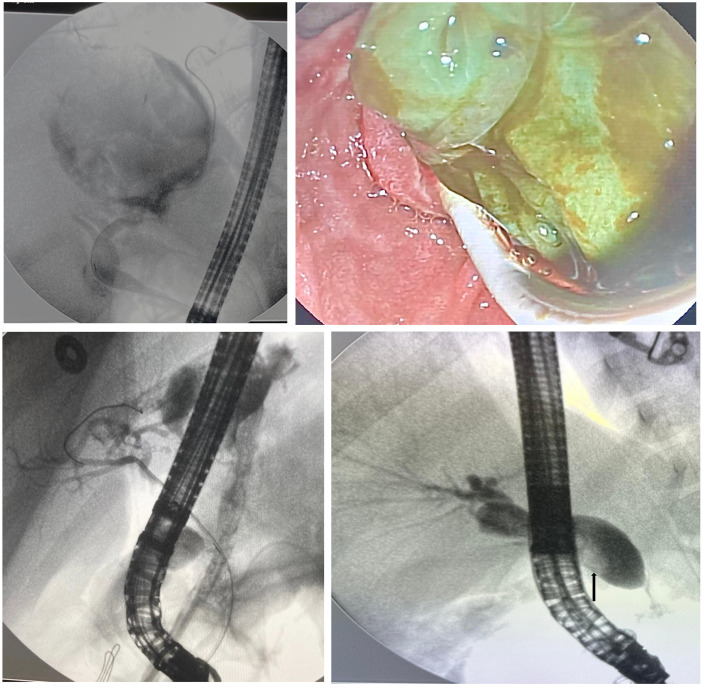

Results: A total of 153 ERCP procedures were performed on 83 pediatric patients (64%, female) with a mean age of 12.9 years (range 3-17) at the time of ERCP. Common bile duct stones were the most frequent indication (n = 39, 47%) for ERCP, followed by biliary hydatid cyst-related complications (n = 24, 29%). The overall cannulation success rate was 98.7% (82/83). Endoscopic sphincterotomy was performed in 79 (95%) patients. More than one ERCP procedure was performed in 41 (49%) patients. Stones were extracted in 32 patients (30 were biliary and 2 pancreatic). Stent placement was performed in 33 patients (25 biliary and 8 pancreatic). Post-ERCP pancreatitis developed in 4.8% (n = 4) of patients, and all classified as mild. Ten (12%) patients developed mild/moderate cholangitis following ERCP. One patient (1.2%) experienced minor bleeding. About half of the patients (48%) were discharged within 1 day postprocedure. No patient experienced procedure-related mortality.

Conclusion: Our study results indicate that ERCP is both effective and safe in the pediatric population.